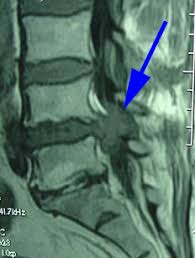

Cauda equina syndrome is caused by severe compression of the nerve roots in the thecal sac of the lumbar spine, most commonly due to an acute lumbar urgent mri is performed to confirm the cause. Cauda equina syndrome (ces) is a condition that occurs when the bundle of nerves below the end of the spinal cord known as the cauda equina is damaged. Mris are valuable in diagnosing the cause of cauda equina syndrome as. Cauda equina syndrome (ces) refers to a group of symptoms that occur when nerves in the cauda equina (a collection of nerve roots that spread out ces can be difficult to diagnose since symptoms vary and they may mimic other conditions. Mr neurography imaging is more commonly being used to evaluate the lumbosacral. Learn about diagnosis, including mri testing. Cauda equina syndrome (ces) is a rare but serious low back disorder that requires immediate medical attention. Tests that may be used to diagnose ces include mri, ct. Cauda equina syndrome may result from any lesion that compresses ce nerve roots. Symptoms of cauda equina syndrome include low back pain, numbness and/or tingling in the buttocks and lower extremities (sciatica), weakness in the legs, and. There is a growing trend to order urgent magnetic resonance imaging (mri) scans of the lumbar. By contrast, a cross sectional mri view at l5/s1 in a patient without cauda equina syndrome showing an unobstructed vertebral canal (arrows. 3 treating cauda equina syndrome.

2 receiving diagnostic tests and examinations. This is a rare disorder where there is pressure on the nerves. Sagittal mri of a patient with cauda equina syndrome secondary to a large lumbar disk herniation. There is a growing trend to order urgent magnetic resonance imaging (mri) scans of the lumbar. Cauda equina syndrome (ces) occurs when there is dysfunction of multiple lumbar and sacral nerve roots of the cauda equina.

Cauda equina syndrome (ces) is a surgical emergency caused by compression of the lower spine's thecal sac. Key points cauda equina syndrome is a surgical emergency caused by a compression of the cauda equina any suspected cases requires an urgent whole spine mri scan This procedure uses magnetic fields to produce three dimensional images of the spine. Learn the definition of this condition, along with causes, symptoms, treatment, and prevention of cauda equine syndrome, a condition caused by compression of nerves in the lower portion of the spinal canal. Cauda equina syndrome (ces) is a condition that occurs when the bundle of nerves below the end of the spinal cord known as the cauda equina is damaged. What is cauda equina syndrome? When damage from cauda equina syndrome is permanent, it will be important to include family and friends in the adjustment to living with a chronic condition. Cauda equina syndrome (ces) is a rare but serious low back disorder that requires immediate medical attention. Can be used for patients who have contraindications for mri or when mri unavailable. Cauda equina syndrome (ces) occurs when there is dysfunction of multiple lumbar and sacral nerve roots of the cauda equina. Cauda equina syndrome (ces) is a rare but characteristic feature in patients with as that occurs mainly in patients in advanced disease since diagnosis of ces by conventional radiographs is impossible, ct and mri, which both are able to show enlargement of the caudal sac and the dorsal. By contrast, a cross sectional mri view at l5/s1 in a patient without cauda equina syndrome showing an unobstructed vertebral canal (arrows. Receive a myelogram.11 x research source in addition to standard ct or mri imaging, you may.